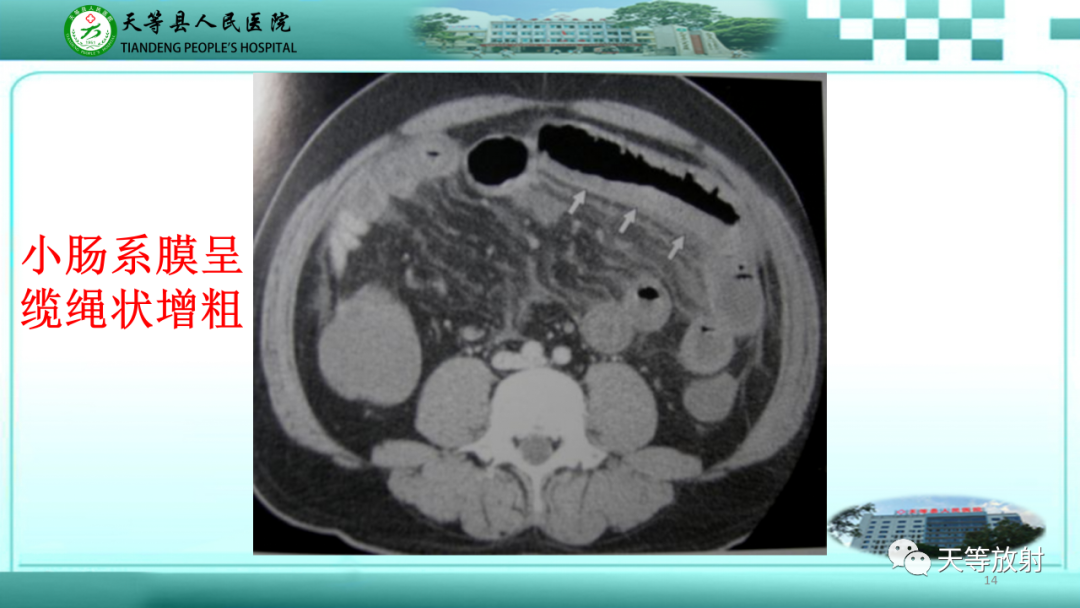

【PPT】缺血性肠病的影像学表现-14